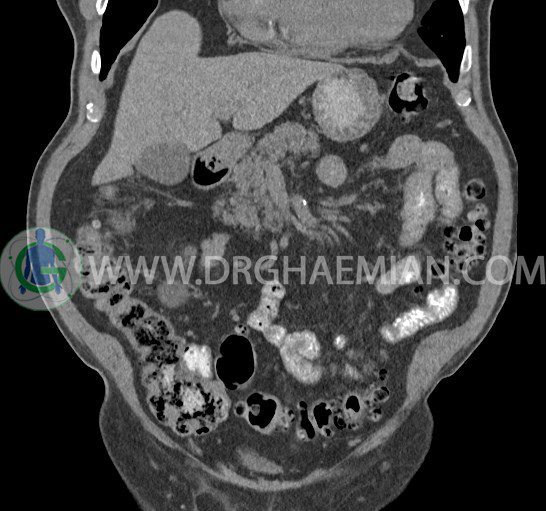

سی تی اسکن لگن یکی از روش های تصویربرداری با سی تی اسکن است. این روش با استفاده از تشعشعات تصاویر عرضی از ناحیه شکمی ایجاد میکند. در این کیس ديورتيكولوزيس، کیست های کورتیکال در هر دو کلیه، لنفادنوپاتی، کلسیفیکاسیون دیواره آئورت و شریان ایلیاک، تغییرات DJD ناحیه توراکولومبار و پروستات بزرگتر از عادی دیده می شود.

در سي تي اسکن اسپيرال شکم و لگن با و بدون کنتراست خوراکی و وريدی (مولتي ديدکتور 16 با مقاطع ظريف و بازسازي هاي ساژيتال و کرونال):

– توده ايزودنس به ابعاد mm 17 x 28 در پره ائورت مجاور قسمت تحتاني D3 دئودنوم مطرح کننده لنفادنوپاتي و با احتمال کمتر آنوريسم ترومبوزه (نيازمند مطابقت سونولوژيک)

– کلسيفيکاسيون ديواره آئورت و شريان ها ايلياک همراه با نشانه هاي ترومبوز مورال در بيفورکاسيون ائورت با امتداد به پروگزيمال هاي شريان هاي ايلياک

لنفادنوپاتي به ابعاد mm 22 x 25 مجاور شريان ايلياک خارجي چپ و به ابعاد mm 17 x 28 مجاور شريان ايلياک خارجي راست

– پروستات به ابعاد mm 45 x 54، بزرگ تر از نرمال

مشهود است.